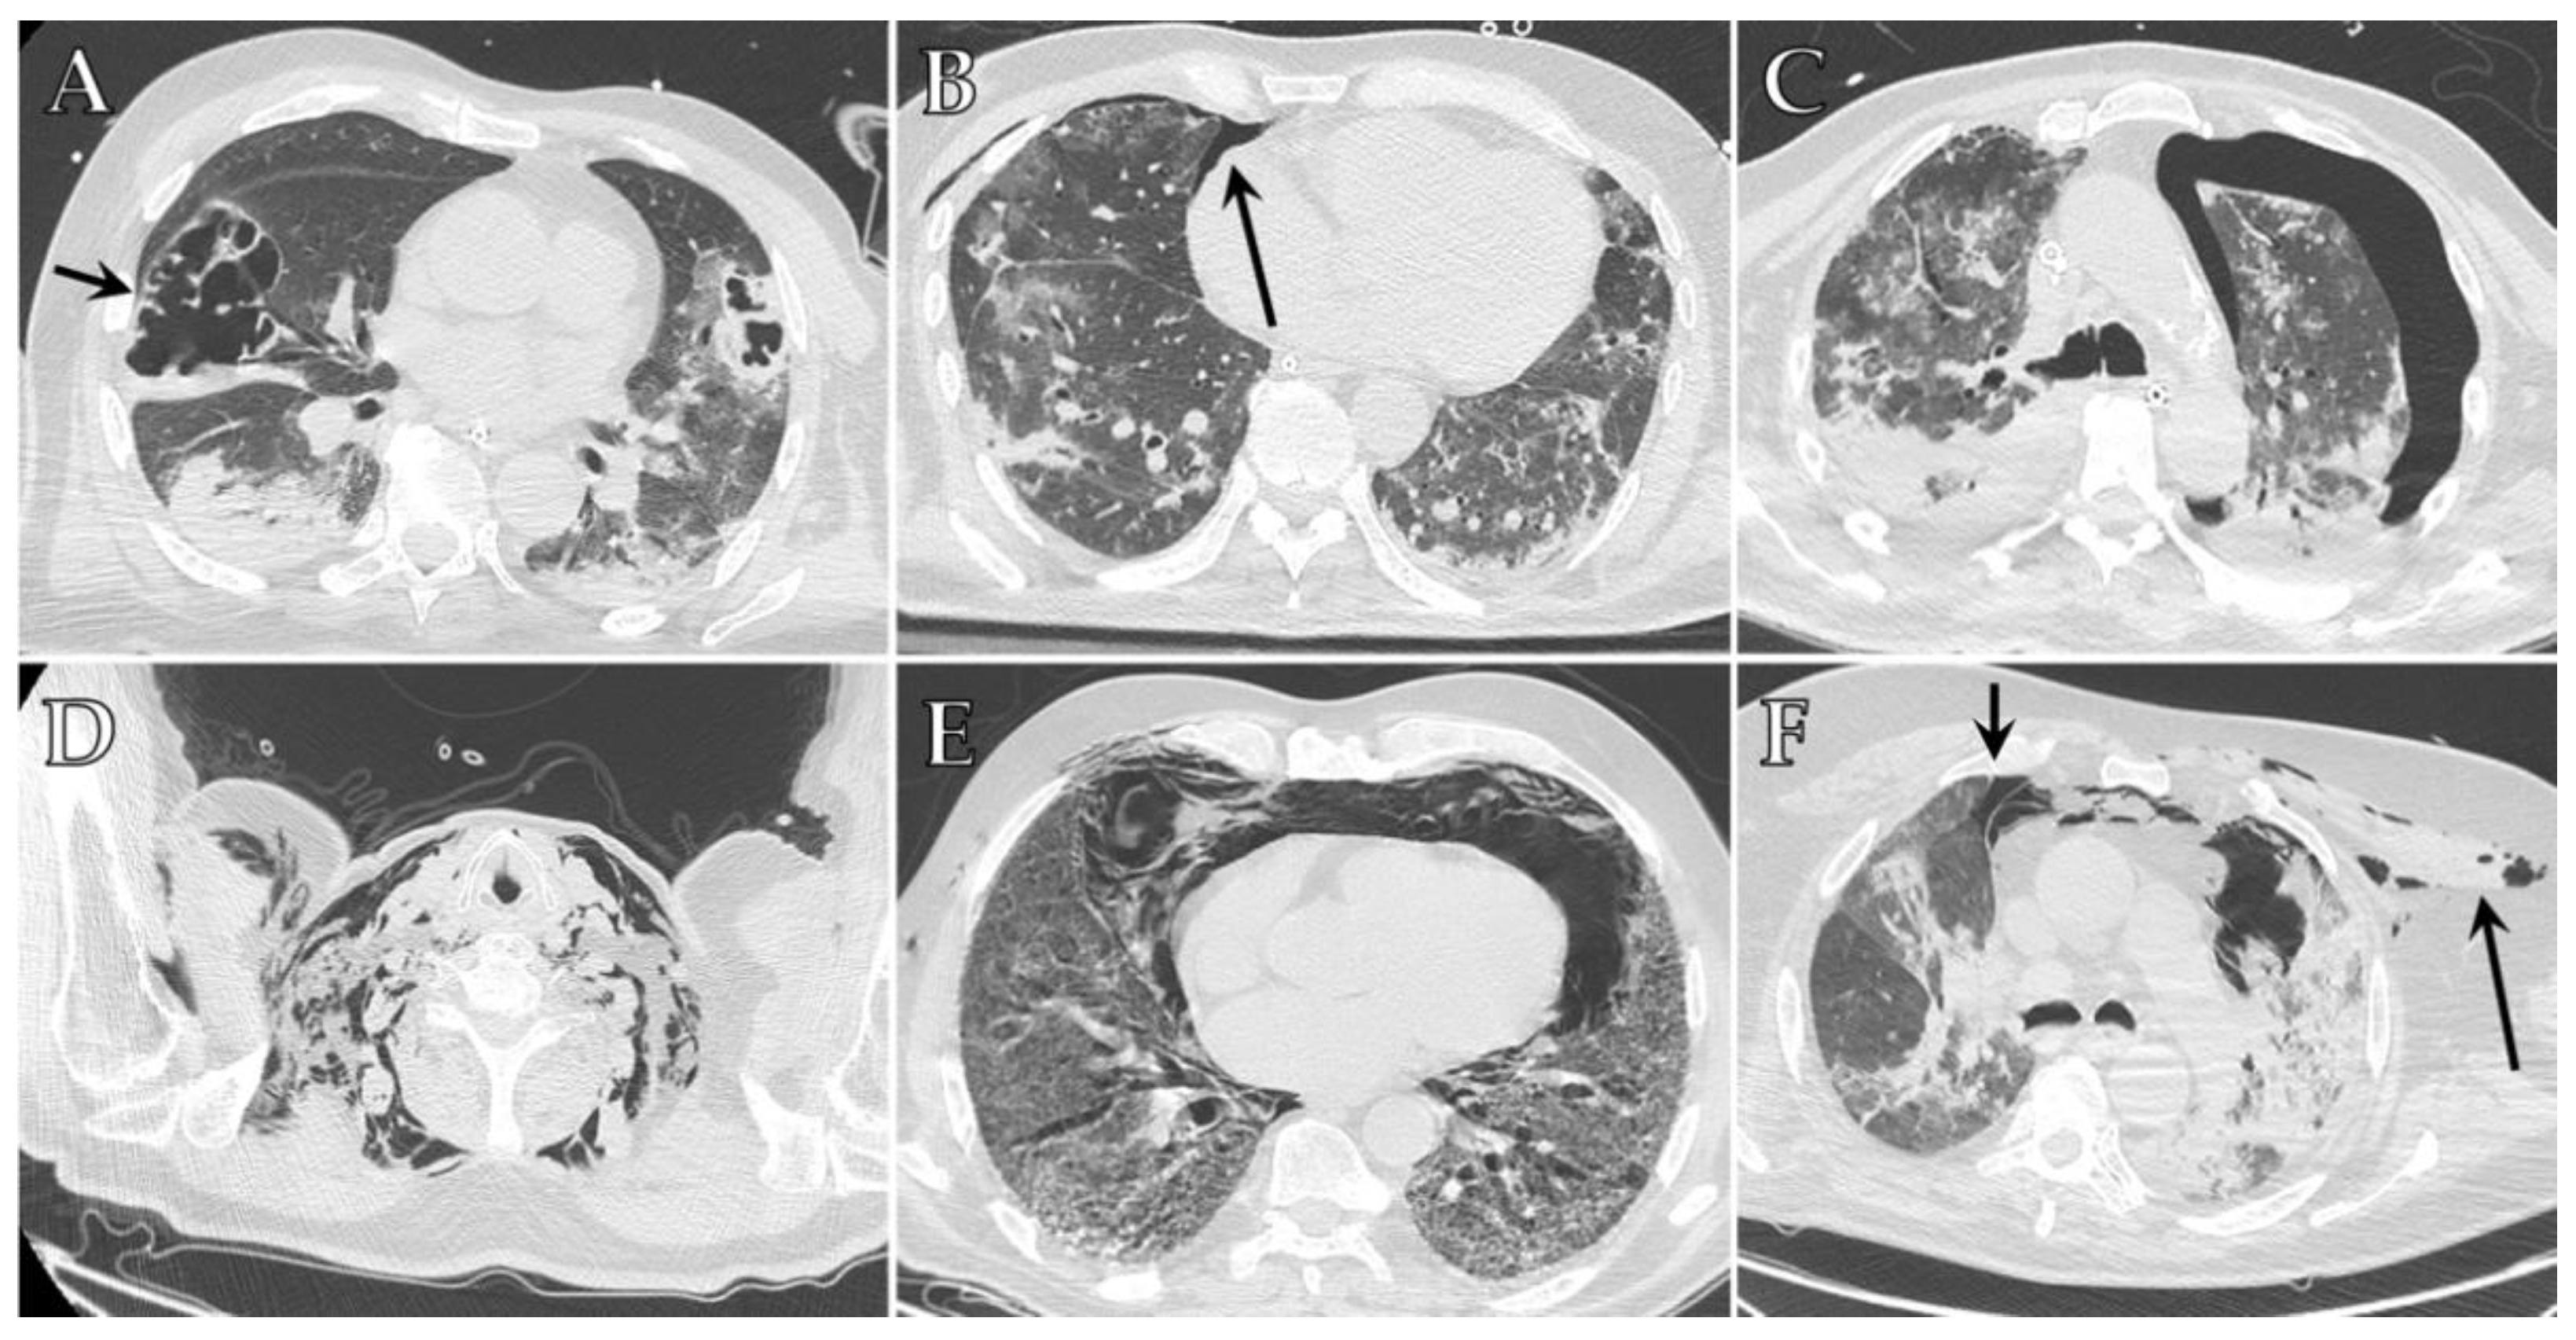

5. Ventilator-Associated Pneumonia (VAP) and Invasive Pulmonary Aspergillosis (IPA)